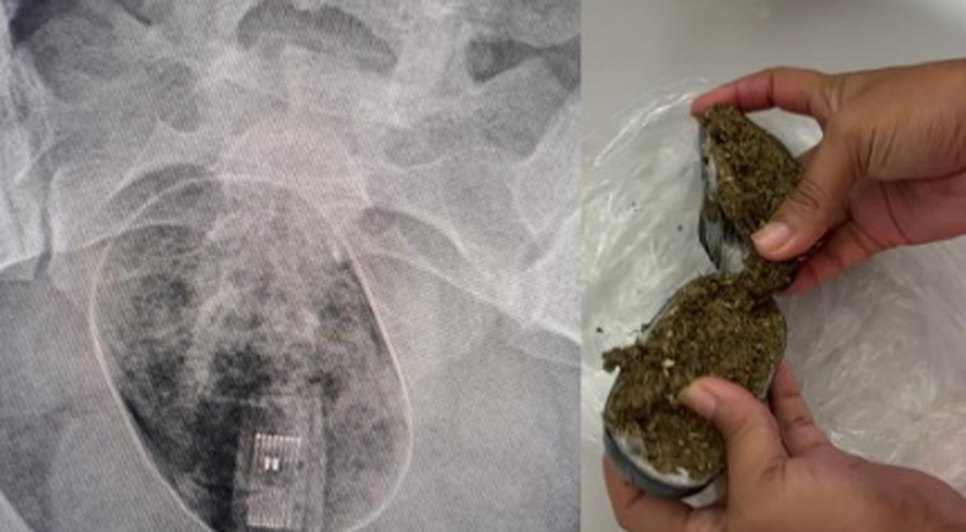

Na última quinta-feira (21), uma mulher foi levada ao Hospital Geral do Estado (HGE) após uma ousada tentativa de entrar no presídio Baldomero Cavalcanti, localizado no Complexo Prisional de Maceió, com pacotes de drogas e um pendrive inseridos em suas partes íntimas. A tentativa criminosa foi detectada durante a revista com o equipamento de bodyscan pela Polícia Penal, que identificou a presença de dois pacotes, um contendo substâncias ilícitas e o outro com um pendrive. A mulher conseguiu expelir o pacote com o pendrive, mas o segundo pacote permaneceu em seu corpo, necessitando de cirurgia para sua retirada.

Segundo informações da Secretaria de Ressocialização e Inclusão Social (Seris), a paciente foi inicialmente encaminhada à Unidade de Pronto Atendimento (UPA) devido à impossibilidade de retirar o pacote com drogas do seu corpo. Posteriormente, devido à necessidade de intervenção cirúrgica, ela foi transferida para o Hospital Geral do Estado.